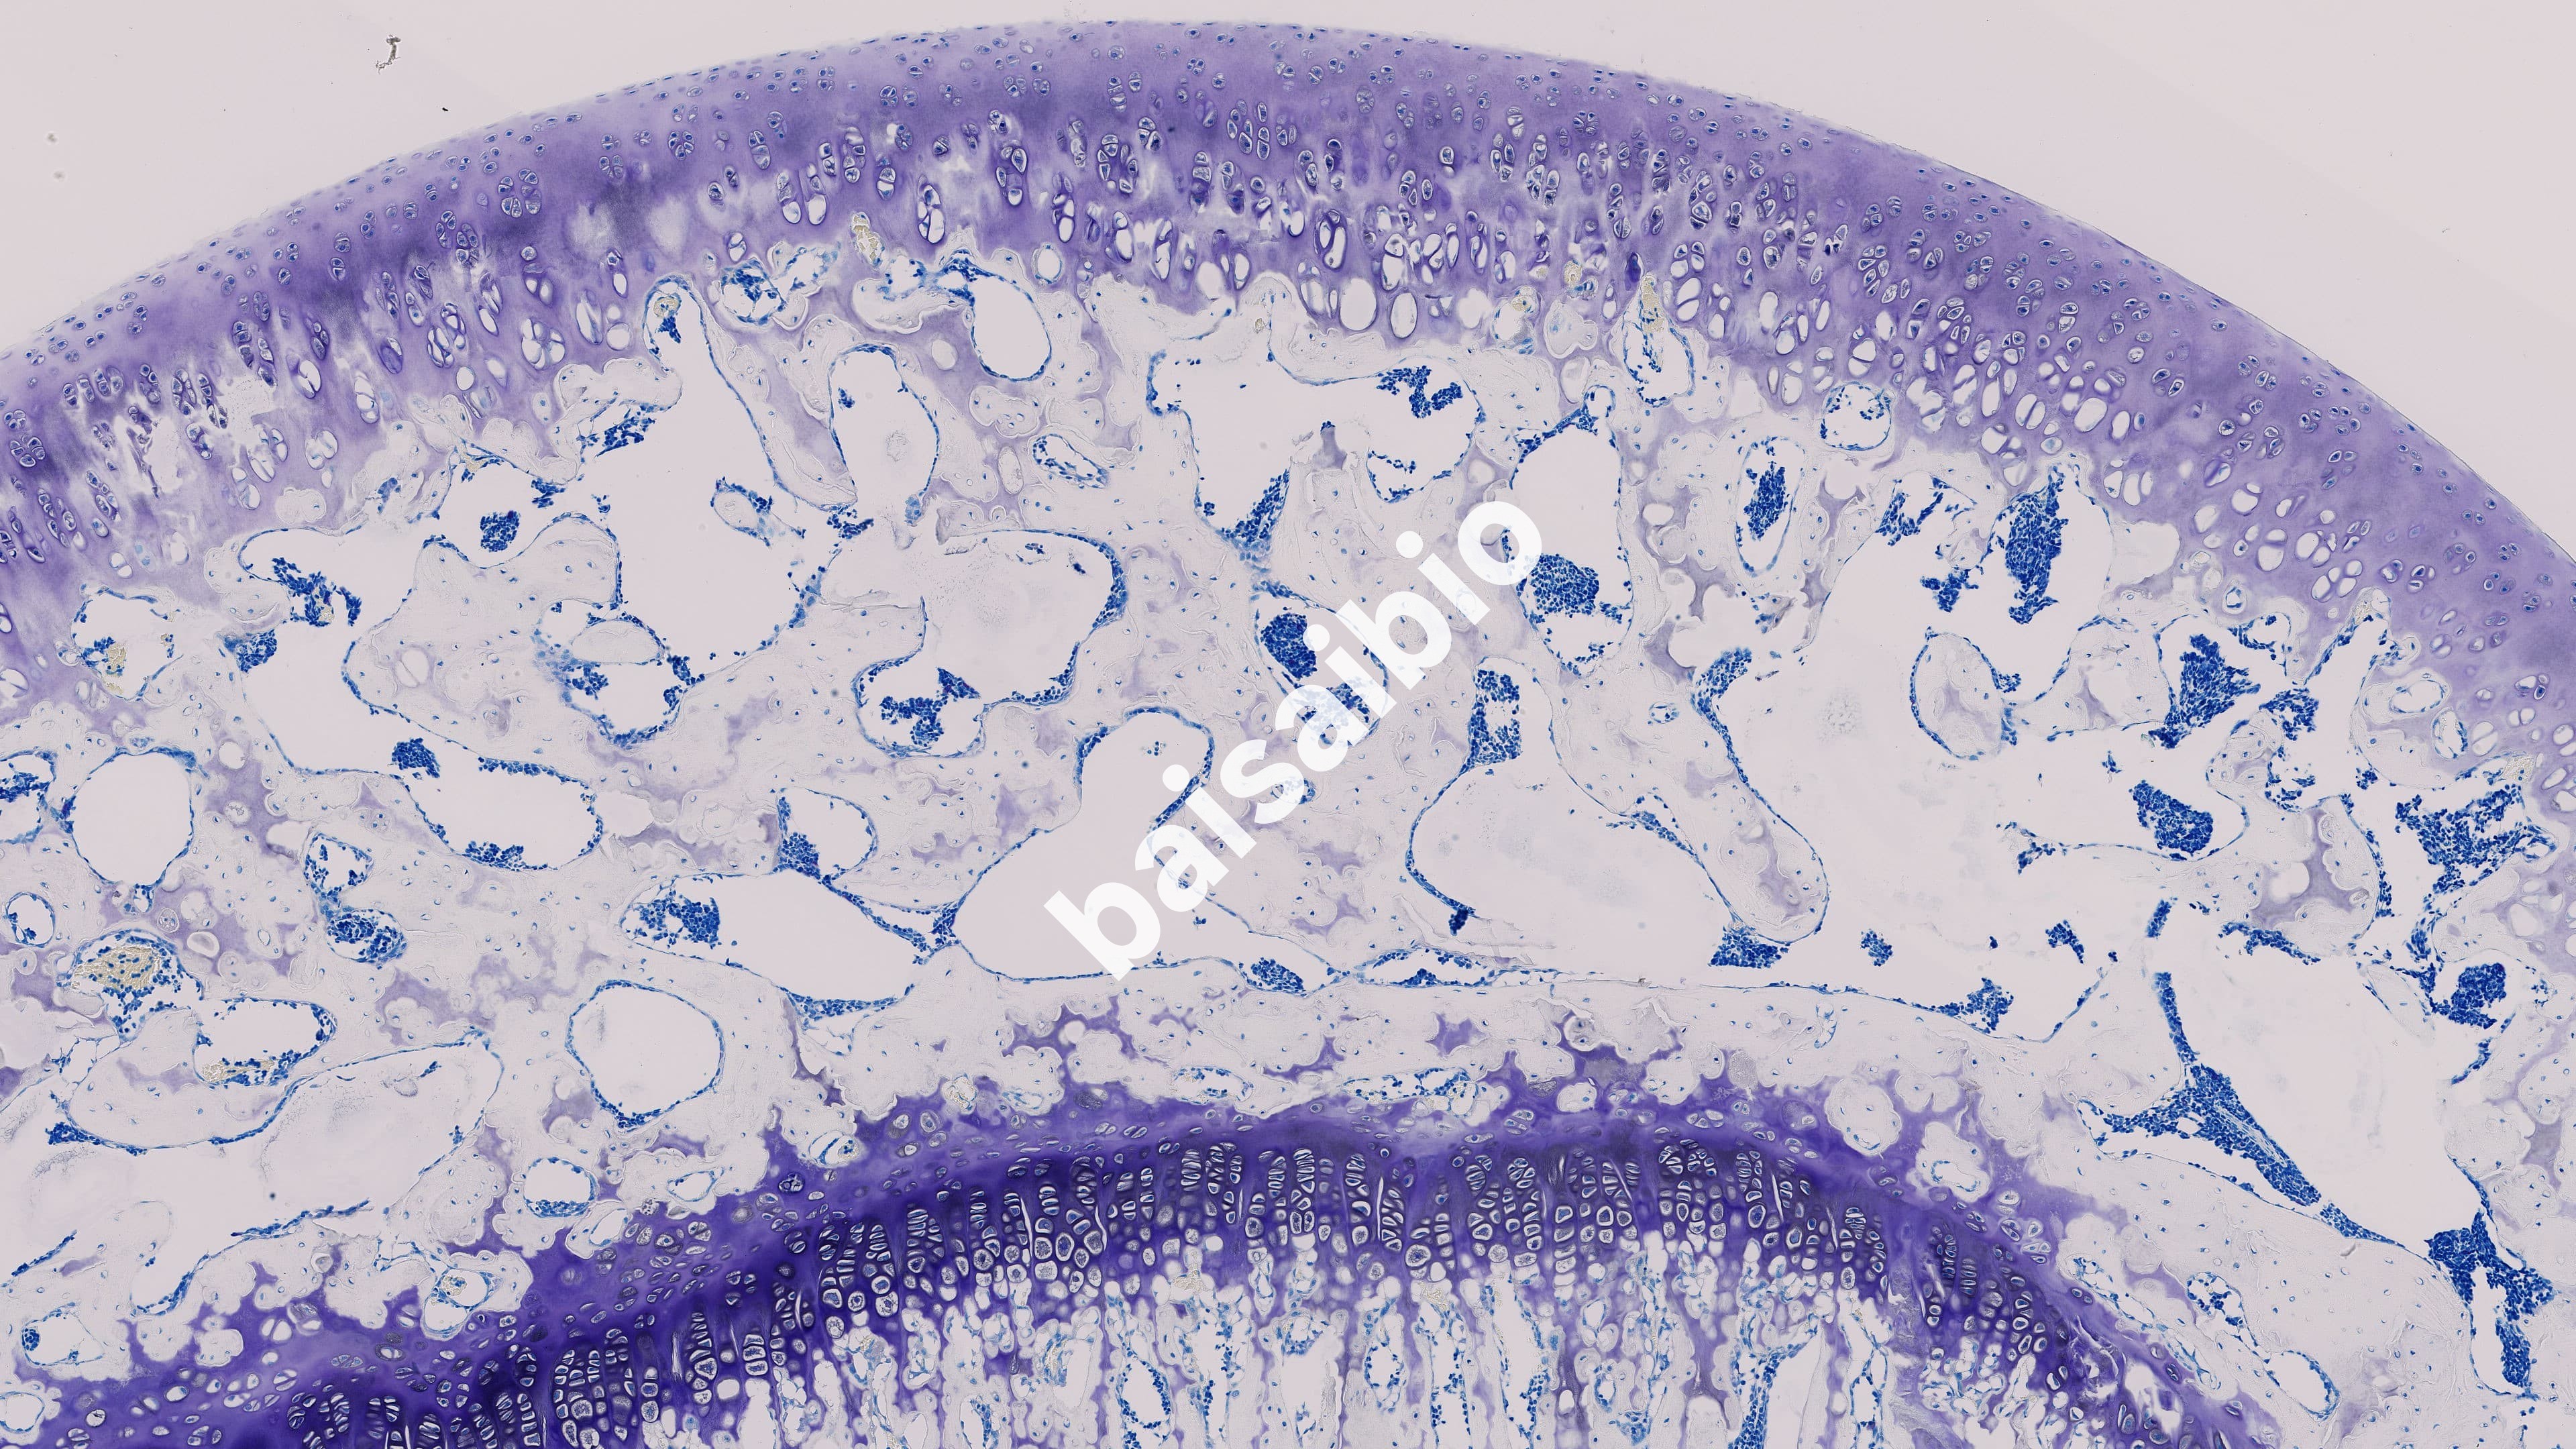

甲苯胺蓝(Toluidine blue)中的阳离子有染色作用,组织细胞的酸性物质与其中的阳离子相结合而被染色。可染细胞核使之呈蓝色;肥大细胞胞质内含有肝素和组织胺等异色性物质遇到甲苯胺蓝可呈异染性紫红色,可用于尖锐湿疣的初筛及肥大检测。